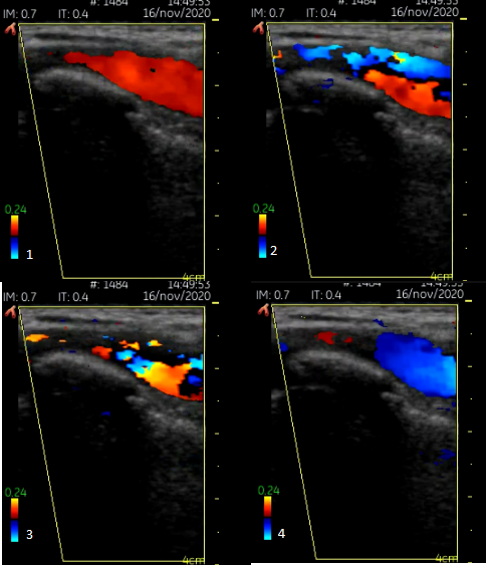

En la exploración se evidencia una masa pulsátil a nivel supraclavicular izquierdo, en triángulo posterior cervical, con un aspecto de ambas extremidades (desarrollo muscular, color, temperatura y distribución de vello y faneras) uniforme. Para comprobar la integridad del flujo vascular de la extremidad se efectúan las maniobras de Adson (persiste pulso radial con la abducción del brazo y la rotación lateral del cuello hacia el lado explorado) y de Wright (abducción de la extremidad hasta los 180 º en rotación externa) que fueron negativas; la tensión arterial bilateral, la auscultación y el electrocardiograma también fueron normales. (Figura 1)

En la misma consulta se realiza una ecografía con ecógrafo de bolsillo y sonda de alta frecuencia (7,5 MHz): se observa flujo turbulento bicolor al aplicar el Doppler, con formaciones irregulares rodeando luz (Figura 2).

La paciente acude de nuevo a consulta con preocupación por latido persistente en cuello, el cual es posible evidenciar por simple observación externa. Se realiza nuevo ecodoppler visualizando un intenso flujo bicolor en arteria dilatada. Ante la posibilidad de tratarse de un desarrollo aneurismático se deriva a urgencias hospitalarias.